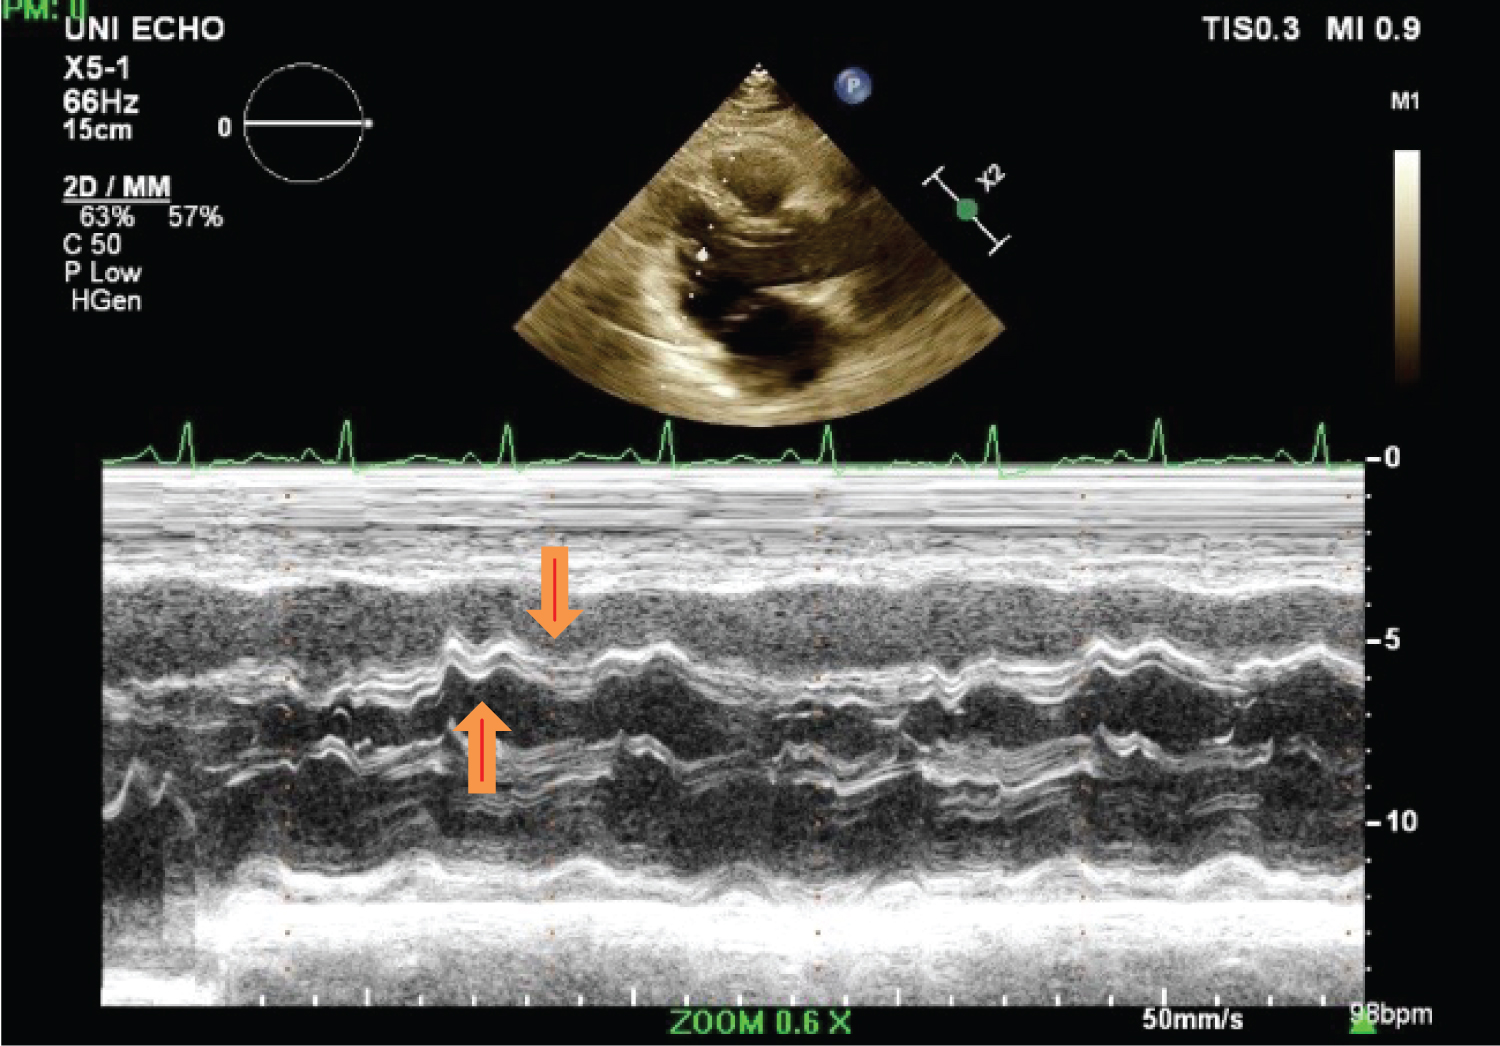

A Thoracentesis was performed revealed transudative pleural fluid, negative for malignancy and negative AFB culture. Serum ANA and anti-ds-DNA levels were normal. Viral serologies including HIV were nonreactive. Transthoracic echocardiogram revealed normal left ventricular ejection fraction (LVEF) of 55%, thickened pericardium with evidence of myocardial-pericardial tethering of left ventricular apical segments and signs of ventricular interdependence. There was leftward deviation of the interventricular septum during early diastole followed by “bounce back” or rightward deviation with late diastolic filling due to the lack of pericardial compliance, also known as “septal bounce”, highly suggestive of constrictive pericarditis (Figure 1 and Video 1).

Figure 1: M-mode echocardiogram showing interventricular dependence with inspiratory bulge of the interventricular septum from right to left (downward arrow) and left to right bounce with expiration (upward arrow). View Figure 1